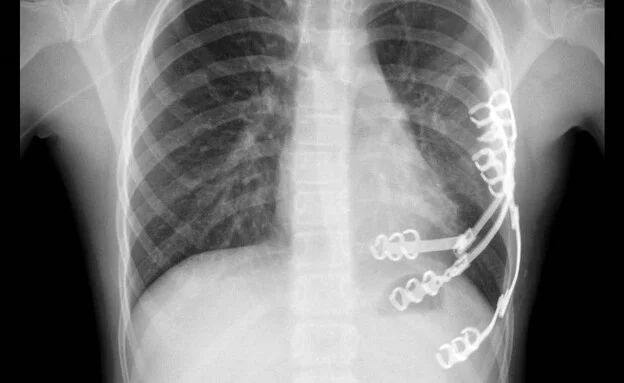

ויולטה הגיעה לישראל במסגרת תיירות מרפא, לאחר שהגידול בגופה הפך בלתי ניתן לשליטה. במשך חודשים עברה תשעה סבבים של כימותרפיה, עד שניתן היה לגשת לניתוח. הסרת הגידול כולו יחד עם חלק מכלוב הצלעות שנפגע, והשתלת שתלים מיוחדים עשויי טיטניום במקומו.

מדובר בניתוח ראשון מסוגו בבית החולים, שנוהל בשיתוף פעולה בין צוותים מבתי החולים שניידר ובילינסון, בהובלת דוקטור יורי פייסחוביץ מבילינסון ודוקטור מיכאל סגל משניידר.